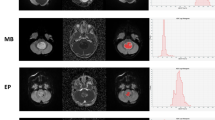

In this retrospective study, we evaluated the distribution of absolute and normalized ADC values of medulloblastomas. Tumors were manually segmented and diffusivity metrics calculated on a pixel-by-pixel basis. We calculated a variety of first-order histogram metrics from the ADC maps, including entropy, minimum, 10th percentile, 90th percentile, maximum, mean, median, skewness and kurtosis, to differentiate molecular and histological variants. ADC values of the tumors were also normalized to the bilateral cerebellar cortex and thalami. We used the Kruskal–Wallis and Mann–Whitney U tests to evaluate differences between the groups. We carried out receiver operating characteristic (ROC) curve analysis to evaluate the areas under the curves and to determine the cut-off values for differentiating tumor groups.

We found 65 children with confirmed histopathological diagnosis of medulloblastoma. Mean age was 8.3 ± 5.8 years, and 60% (n = 39) were male. One child was excluded because histopathological variant could not be determined. In terms of medulloblastoma variants, tumors were classified as classic (n = 47), desmoplastic/nodular (n = 9), large/cell anaplastic (n = 6) or as having extensive nodularity (n = 2). Seven other children were excluded from the study because of incomplete imaging or equivocal molecular diagnosis. Regarding medulloblastoma molecular groups, there were: wingless (WNT) group (n = 7), sonic hedgehog (SHH) group (n = 14) and non-WNT/non-SHH (n = 36). Our results showed significant differences among the molecular groups in terms of the median (P = 0.002), mean (P = 0.003) and 90th percentile (P = 0.002) ADC histogram metrics. No significant differences among the various medulloblastoma histological variants were found.